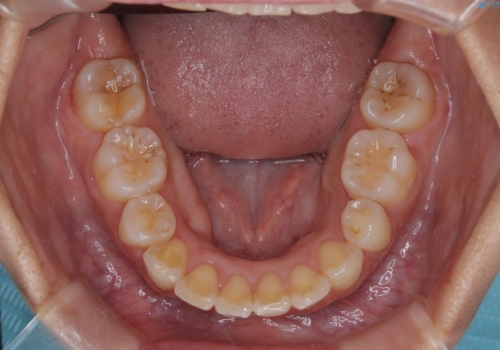

凸凹を綺麗にしたい。表側ワイヤー矯正

- 前歯の凸凹を主訴に来院されました。

抜歯を行い、ワイヤー矯正にて治療を行いました。

凸凹もなくなり、歯磨きもしやすくなったと喜んでいただきました。

CTにて骨を確認し、側切歯の歯根をこれ以上頬側に出せないことを確認しています。